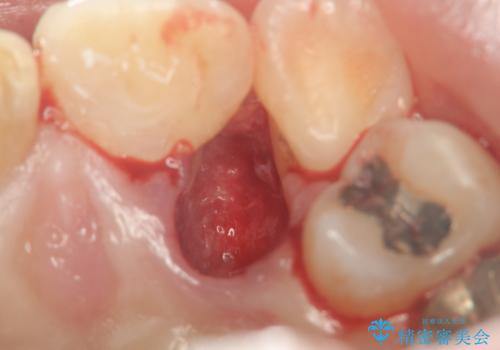

歯ブラシがしづらく虫歯の原因となっている歯の位置の悪い右上側切歯の抜去を行います。

清掃を難しくしている歯を抜去することで虫歯の再発を防ぐような治療方針としました。